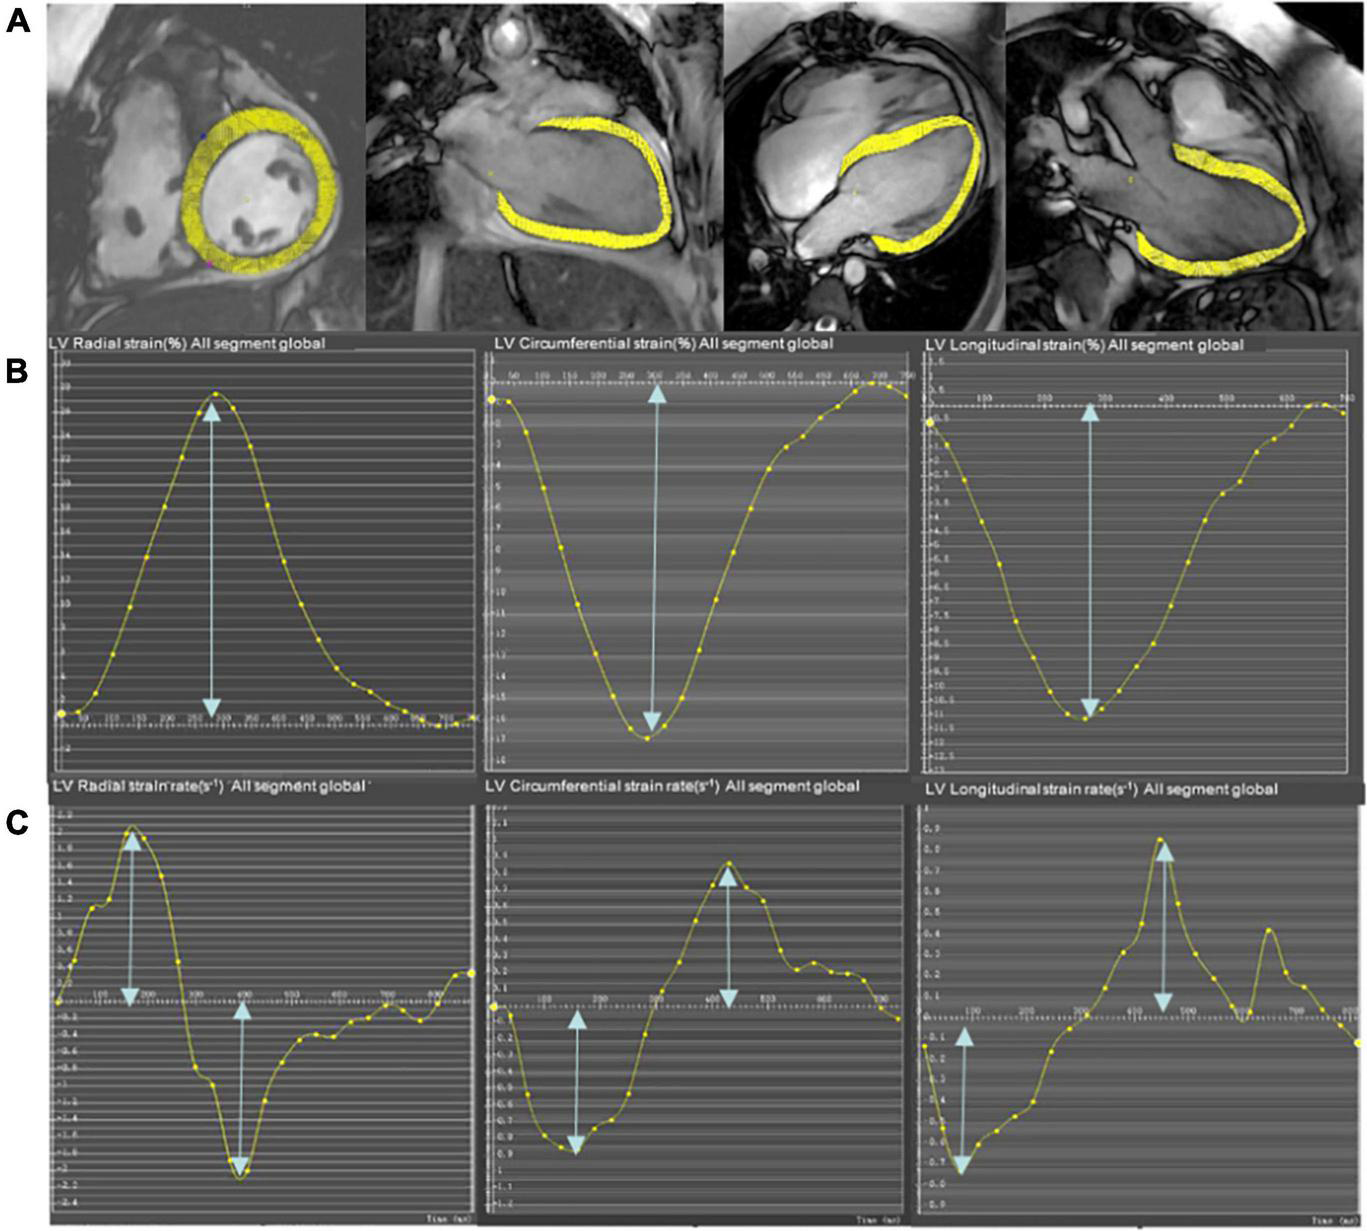

The global cardiac strain and strain rate representing the average of the entire heart were calculated from CMR cine images using the mature feature tracking software CVI 42 version 5.12. The method has been described in detail in a previous study (15). In brief, the LV 4-chamber, LV 3-chamber, and LV 2-chamber were selected for post-processing to calculate the peak longitudinal strain (LS), peak systolic strain rate, and peak early diastolic strain rate (LSRe). The entire LV short-axis SSFP cine images were analyzed for radial strain (RS), circumferential strain (CS), peak systolic strain rate (RSRs and CSRs), and early diastolic strain rate (RSRe and CSRe). The endocardial and epicardial borders of the LV were semi-automatically defined using the AI function of the CVI following manual adjustments. The peak radial, circumferential, and LSs of the LV were identified as the highest or lowest peak of the global strain curve. Similarly, the peak systolic and early diastolic strain rates of the LV were calculated as the highest or lowest peak of the global strain rate curve (Figure 1) (24).

FIGURE 1

Representative short-axis and long-axis images (A), strain curves (B), and strain rate curves (C) in a participant who underwent pulmonary valve replacement (PVR). The epicardial and endocardial borders (excluding papillary muscles and trabeculae) at end-diastole are semi-manually defined in the LV 4-chamber, LV 2-chamber, and LV 3-chamber to calculate longitudinal strain and strain rate. The entire LV short-axis SSFP cine images are used to calculate radial and circumferential strain and strain rate.